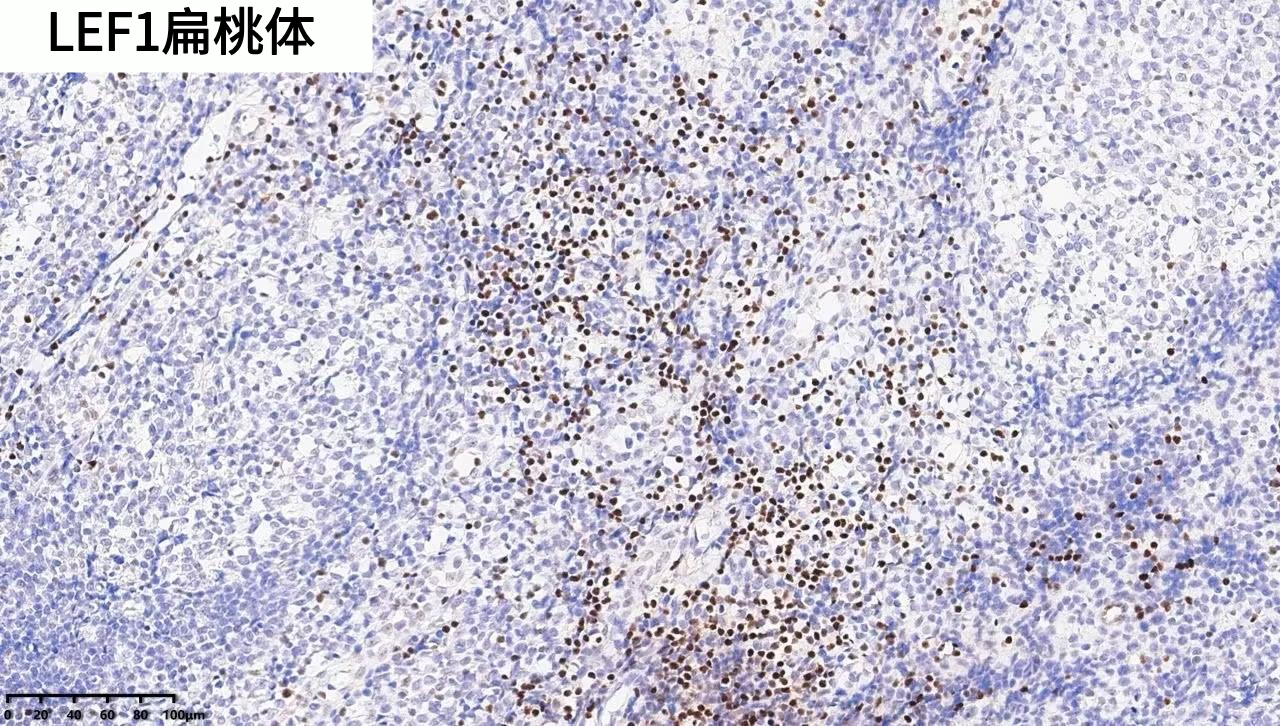

LEF-1 | ZA-0619 | EP310 | 細胞核 | 闌尾/扁桃體 |

產(chǎn)品染色圖賞析

其他腫瘤類(lèi)型:在包括纖維瘤病等多種腫瘤類(lèi)型中,LEF1與WNT通路所有檢測到的突變顯著(zhù)相關(guān)。LEF1作為CTNNB1突變替代標志物在多種實(shí)體瘤中表現良好,準確性更高,因其簡(jiǎn)單的染色結果(彌漫性核過(guò)表達或無(wú)染色)和組織內T細胞作為內部陽(yáng)性對照,比β -連環(huán)蛋白更易解讀。